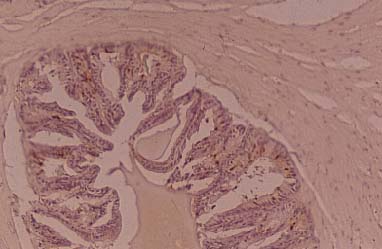

Although all individuals of cats examined were grouped into blood group A, they were classified into two subgroups according to the difference in the distribution of A and H antigens in the submandibular gland. In one group of cats, A antigen was expressed both in the mucous and duct cells of the gland but the H antigen was found only in the duct cells (Fig.1 a, b). In another group, pattern of the expression of these antigens was reverse, i. e., H antigen was expressed both in mucous and duct cells while A antigen was expressed only in duct cells. Similar difference in staining patterns with anti H or A MoAbs were also recognized in the serous cells of von Ebner's gland and mucous cells of lingual gland in the tongues. In both groups, Le x and Le y MoAbs stained the duct cells of submandibular glands (Fig.1 c, d). Anti Le y MoAbs stained moderately the serous cells of von Ebner's gland, weakly the mucous cells of the lingual glands and strongly the duct cells of submandibular glands and lingual glands (Fig.1 d). Anti Le x MoAbs showed weak reactivity with the duct of other glands Anti A and/or H MoAbs stained the taste bud cells corresponding to the reactivity in the salivary gland of individuals (Fig.1 c). The taste bud cells were moderately stained by Le y and feebly by Le x MoAb. Anti Le a and Le b MoAbs showed no reactivity with the secretory cells of salivary glands and taste bud cells of cats. The reactivity with anti A and/or H MoAbs were observed in all of the individuals of cats examined.

The epithelial cells of proximal tubules of cat kidneys were stained with anti A, Le y and Le x MoAbs (Fig.3 a, c, d). The positive reaction was recognized exclusively in the Golgi region of the cells. Anti H (Fig.3 b), Le a and Le b MoAbs showed no reactivity with the cells in the kidney. In this study, the examination of the prostates of cats was not performed since the organs could not be obtained. Anti A MoAbs and HPA lectin showed good reactivity with the epithelial cells of epididymis including secretory fluid and spermatozoa in the lumen of epididymis (Fig.4). Le x and Le y MoAbs showed weak reactivity with the epithelial cells of ductus efferent.